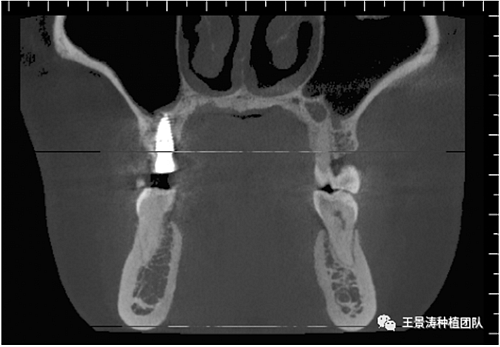

左側(cè)下頜第二磨牙及右側(cè)下頜第一磨牙同時(shí)即刻種植病例?;颊吣贻p女性,無系統(tǒng)性疾病。37及46殘冠及殘根,且46劈裂,無法冠修復(fù),必須拔除。37根尖慢性炎癥,大量肉芽組織存在,46根分叉較高,根分叉骨質(zhì)尚可。CBCT示:根尖骨質(zhì)至下牙槽神經(jīng)管距離可滿足種植體的初期穩(wěn)定性,遂考慮即刻種植,并在種植體周邊填入骨粉并覆蓋骨膜,雙側(cè)的種植體初期穩(wěn)定性相差無幾,但考慮到37根尖慢性炎癥較大,遂給予埋入式種植。